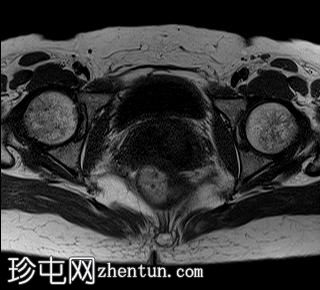

轴位

T2加权像

可见局部晚期浸润性内生型宫颈癌,肿瘤大小为30 x 32 x 48 mm。该肿瘤已侵犯宫颈前唇和后唇的深层间质,以及子宫肌层的下段。

此外,肿瘤还累及宫旁组织。影像学检查发现异常淋巴结肿大,最大短轴直径(SAD)为10 mm,位于髂总血管分叉处和髂内动脉链下方。该淋巴结肿大在弥散加权成像(DWI)上显示水限制,且增强扫描后可见强化。